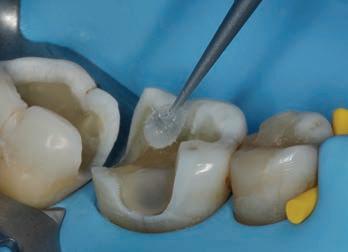

The patient at the first appointment immediately required a quick solution for the pain, consecutive to an incomplete endodontic treatment and a partially removed carious lesion. So, the first step consisted in the removal of the decayed tissue of the distal face of the tooth 25 in its coronal portion and in the first third of the root.

The cervical limit of the decay was exposed; then the wall was restored with a glass hybrid material (EQUIA Forte™, GC) coated with the light-curable EQUIA Forte Coat™ to obtain a more resistant material even in case of occlusal loads. 7-9 A glass hybrid material was chosen because the apical edge of the tooth cavity was under the gingival margin, so it was impossible to obtain a correct isolation for a composite restoration: it’s known that the glass hybrid materials can tolerate acid and humid environments more than composite. 7-9

The glass hybrid EQUIA Forte was preferred to glass ionomer because better long-term results are reported in literature. 7-10

The canal was sealed with a Thermafil™ cone (Dentsply Sirona) with an apical diameter of 0.30 mm (Figs. 3-4).

glass fibre Figure 3: Root canal therapy completed under proper isolation. Figure 4: Radiography of completed root canal therapy and reconstruction made completely in glass hybrid cement. Figure 5: Clinical crown lengthening with a minimally invasive technique without mesial and distal discharges. Note the proximity of the reconstruction in glass hybrid material to the mesial bone ridge. Figure 6: Suture at the end of surgical therapy. It was left in place for 7 days Figure 7: Suture removal at 7 days. Post-surgical edema is still present.